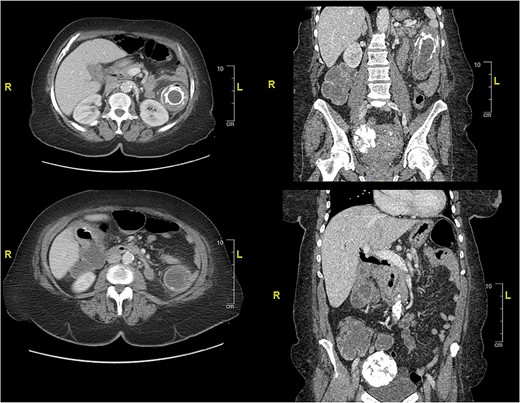

Case presentation # 1: An 80-year-old female with congestive heart failure and hypertension, presented to the emergency room with 4 days of diffuse abdominal pain associated with nausea, vomiting and anorexia. She was hemodynamically stable upon presentation, with upper abdominal tenderness on exam. Initial imaging (Figs 1 and 2) was obtained, showing a CCF with large bowel obstruction caused by an 8-cm gallstone in the descending colon. The patient was taken to the operating room for an exploratory laparotomy, where upon inspection a large gallstone in the descending colon and a fistulous communication between the gallbladder and hepatic flexure of the colon were noted. Takedown of the fistula was attempted, however because of extensive colonic involvement a decision was made to perform a right hemicolectomy with primary anastomosis, as well as a partial cholecystectomy at the level of infundibulum due to chronic inflammation and thickening of the gallbladder. The gallstone was taken out with the specimen (Fig. 3). The postoperative course was significant for exacerbation of heart failure, but ultimately, she was discharged home upon successful tolerance of a regular diet with return of bowel function.

CT of abdomen and pelvis showing an inflamed gallbladder with fistulous communication within the hepatic flexure of the colon. Large descending colon enterolith (4.5 × 4.3 × 8.0 cm). Apparent pneumobilia.